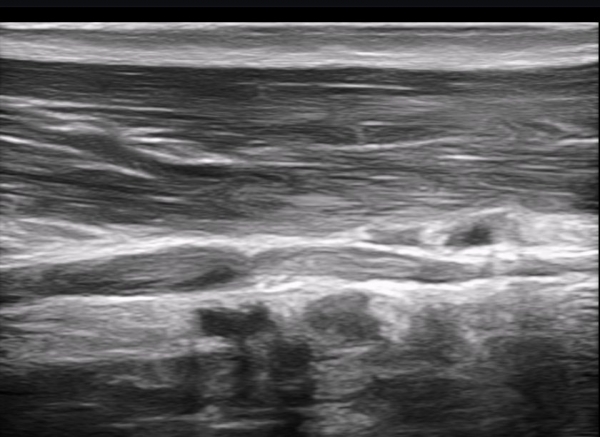

Å½ÃËÀÚ¸¦ Á¶±Ý ¸»´ÜÀ¸·Î À̵¿ÇÏ´Ï ±ÙÀ°ÇǺνŰæÀÇ À§ÃàÀÌ °üÂûµÇ°í(»çÁø 2) ŽÃËÀÚ¸¦ Á¶±Ý ´õ

¸»´ÜÀ¸·Î À̵¿ÇÏ´Ï ±ÙÀ°ÇǺνŰæÀÌ Á¤»êÀûÀ¸·Î °üÂûµÈ´Ù(»çÁø 3).